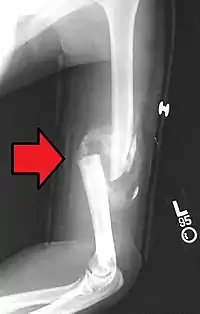

التیام استخوان، یا التیام شکستگی، فرایندی فیزیولوژیکی و رشدی-تکثیری است که در آن ترمیم شکستگی استخوان تسهیل می شود.

عموماً، درمان شکستگی استخوان شامل این مراحل است: پزشک با فشاردادن استخوانهای از جا در رفته به مکانش، از طریق جابجایی با یا بدون بیهوشی، پایدارسازی موقعیتش برای کمک به یکی شدنشان، و سپس انتظار برای انجام فرایند التیام طبیعی استخوان.

فرایند بازتولید کل استخوان، بستگی به زاویه جابجایی یا شکستگی دارد. در حالی که تشکیل اسjخوان اغلب کل فرایند التیام را در بر می گیرد، در برخی موارد، مغز استخوان در قسمت شکستگی، یک الی دو هفته قبل از مرحله آخر بازمدلسازی التیام پیدا می کند.